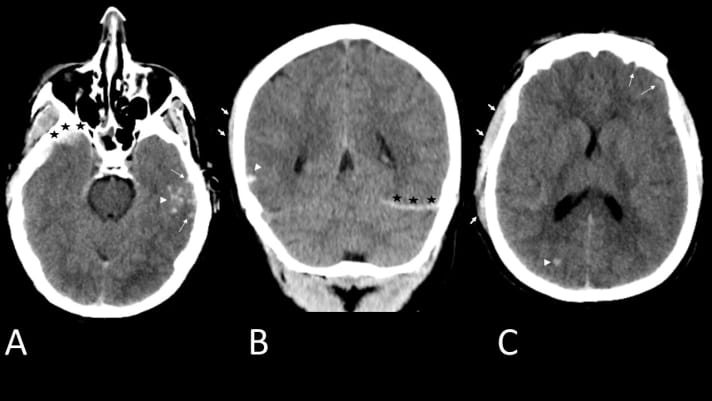

Computertomogramm (CT - ohne Kontrastmittel) des Kopfes eines jungen Mannes nach Schädel-Hirn-Trauma. Man sieht einen Bluterguss (dicke Pfeile in B und C) in und unter der Haut an der Schläfe. Im Schädel (unterhalb der schwarzen Sterne in A und B) findet sich ein Bluterguss zwischen Gehirn und Gehirnhaut. Man sieht auch Blut zwischen den Hirnfurchen (schlanke Pfeile in A und C) und im Hirngewebe selbst (Pfeilspitzen in A-C).Foto: Prof. S. UlmerComputertomogramm (CT - ohne Kontrastmittel) des Kopfes eines jungen Mannes nach Schädel-Hirn-Trauma. Man sieht einen Bluterguss (dicke Pfeile in B und C) in und unter der Haut an der Schläfe. Im Schädel (unterhalb der schwarzen Sterne in A und B) findet sich ein Bluterguss zwischen Gehirn und Gehirnhaut. Man sieht auch Blut zwischen den Hirnfurchen (schlanke Pfeile in A und C) und im Hirngewebe selbst (Pfeilspitzen in A-C).